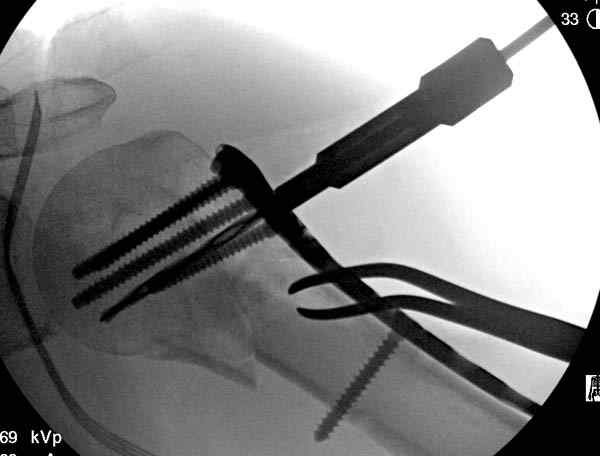

Здесь пример открытой репозиции 57 летнего с переломом плеча (1,2) смещение обнаружено на интероперационном снимке. При нормальной прямой проекция (3) угловое смещение обнаружили в аксиальной проекции (4)

После устранения смещения пластина установлена выше (5,6,7) и финальные снимки (8,9,10)

Подбор импланта тоже имеет значение, например многие импланты направлены для фиксации перелома без учета ротаторной манжетки. Предпочтительными являются низко сидящие полиаксиальные пластины, где верхние шурупы можно проводить под углом в 120 градусов. (11)

Пластина от Synthes или ее копии (надеюсь простят критику друзья из Деоста) считаются трудным из-за обширности доступа, особенно при установке верхне-заднего шурупа, где доступ надо расширять в верхнем отделе до ротаторной манжетки. Верхне сидящие импланты предназначены для проведения опоры (buttress) за бугристость плеча, но тогда приходится сталкиваться с подакромиальным импинжментом.